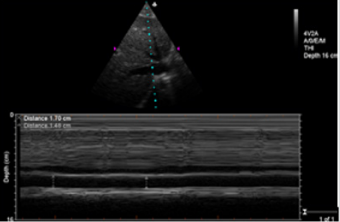

Ultrasonic Testing and PPV Monitoring Method: In complete mechanical ventilation control mode, below indexes were measured by M-Turbo bedside portable ultrasonic apparatus of SonoSite (America): ①CO (cardiac output) ②measuring SV and recording SVV %=(SVmax﹣Svmin)/SVmean, SVmax and SVmin being the mean value of 4 values in 30s, SVmean being the mean value of all values. ③Measurements of IVCdmax , IVCdmin and dIVC were performed from long-axis 2-dimensional subxiphoid views using M mode (Figure1), All measurements were made within 2 cm of the RA origin of the IVC(Figure2), dIVC= (IVCdmax − IVCdmin)/0.5(IVCdmax + IVCdmin) [13]. Ultrasonic testing were respectively conducted by an experienced ultrasound diagnostics doctor and a trained ICU doctor. Each observation indicator was took the average after being measured three times. During mechanical ventilation, the arterial pressure waveform was drawn from invasive arterial pressure monitor, recording PPmax and PPmin, PPV(%)=( PPmax-PPmin) /[(PPmax+PPmin)/2]×100%[20].